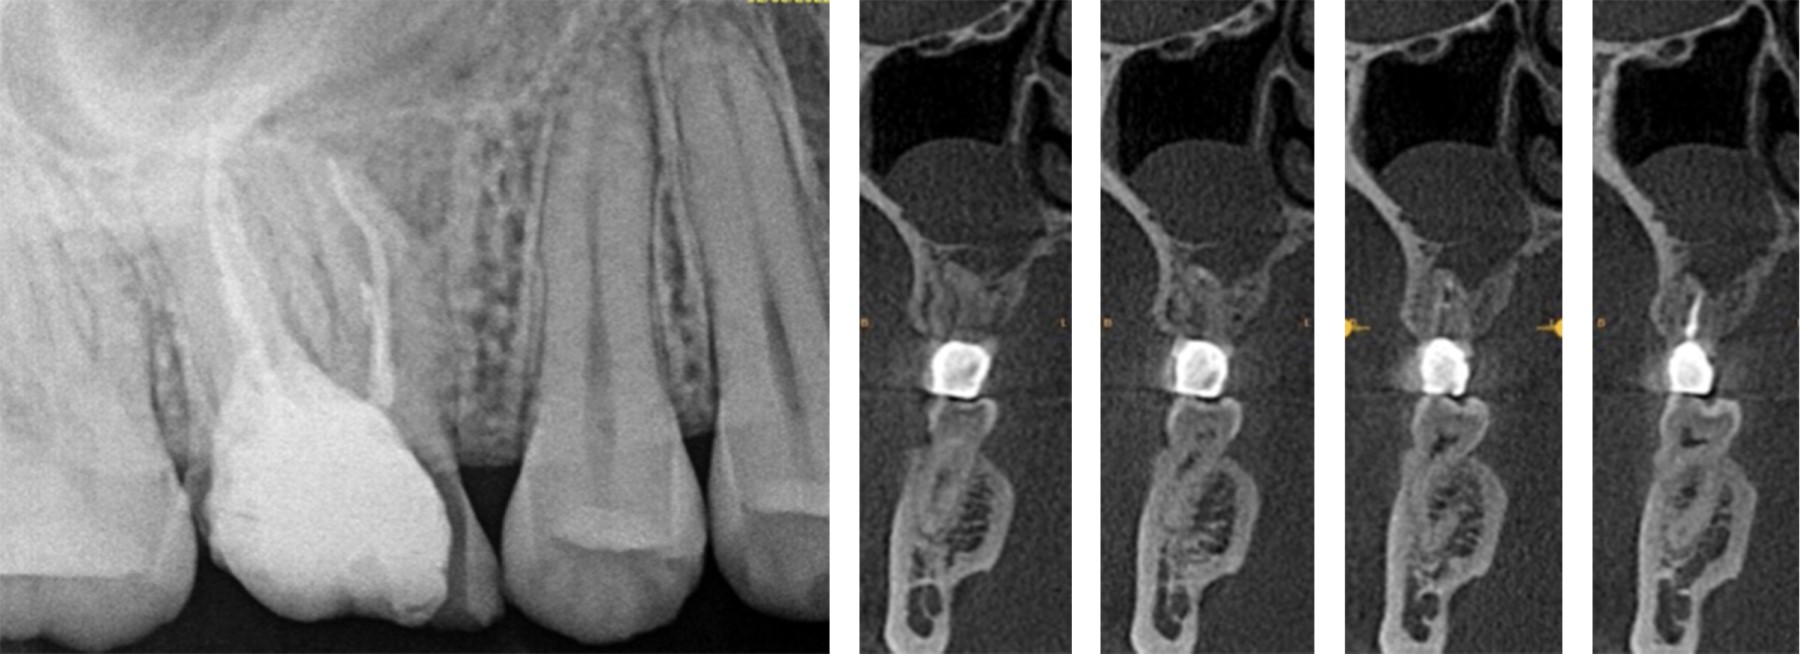

A la exploración clínica, se observó el primer molar superior derecho (OD #16) con aparente reconstrucción protésica, tejido dental remanente deficiente y una recesión palatina de en promedio cuatro milímetros y un sondaje en el sitio palatino de dos milímetros; lo que resulta en una pérdida de nivel de inserción clínica (CAL) de seis milímetros (Figura 1).

Al análisis radiográfico se observó dicho órgano dental con tratamiento de conductos y reconstrucción protésica y, al análisis tomográfico, se muestra un cuerpo radiopaco inusual dentro del seno paranasal derecho (Figura 2).

Figura 1

Figura 2